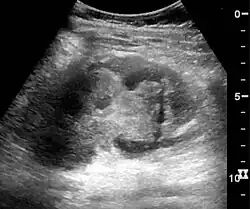

In medical imaging, the acute changes in the kidney are often examined with renal ultrasonography as the first-line modality, where CT scan and magnetic resonance imaging (MRI) are used for the follow-up examinations and when US fails to demonstrate abnormalities. In evaluation of the acute changes in the kidney, the echogenicity of the renal structures, the delineation of the kidney, the renal vascularity, kidney size and focal abnormalities are observed.[20] CT is preferred in renal traumas, but US is used for follow-up, especially in the patients suspected for the formation of urinomas. A CT scan of the abdomen will also demonstrate bladder distension or hydronephrosis.[21]

Renal ultrasonograph in renal failure after surgery with increased cortical echogenicity and kidney size. Biopsy showed acute tubular necrosis.[20] -